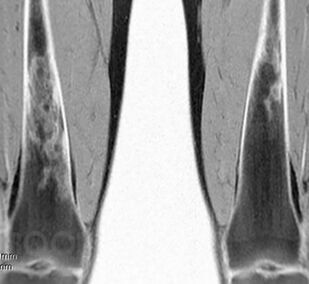

Болезнь Гоше относится к системным заболеваниям неопухолевой природы, в основе которых лежат наследственные дефекты метаболизма, приводящие к накоплению в органах и тканях нерасщепленных продуктов нормального обмена веществ. В случае болезни Гоше дефектом метаболизма является дефицит фермента, ответственного за метаболизм липидов.

Цель книги — познакомить врачей различных специальностей с основными клиническими проявлениями болезни Гоше, продемонстрировать исключительную вариабельность течения болезни на примере конкретных клинических случаев, показать характерные ошибки диагностики и ведения пациентов с болезнью Гоше. Помимо врачей, книга может быть полезной для образования самих пациентов и их родственников, так как некоторые особенности клинического течения заболевания напрямую связаны с социально-бытовыми аспектами: образом жизни, физической активностью, наличием бытовых интоксикаций и др.